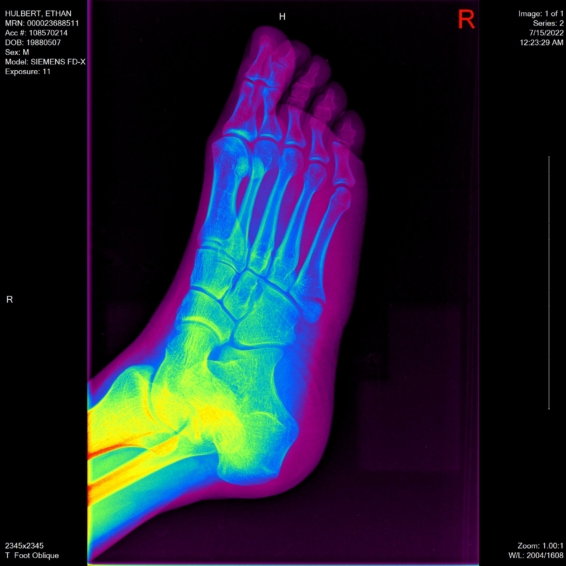

Right Foot: 2022 July

In July of 2022, I broke my right foot. I stepped over a curb wrong, twisted it, and when my weight went down on it, I’m lucky that the muscle didn’t break–instead, it was strong enough to pull one of my bones so hard it cracked it instead.

On the positive side, I got x-rays taken of my right foot from three different angles–the only useful thing Kaiser managed to do.

This software was fantastic. It let me see each x-ray in 7 different view modes, with different settings for brightness, contrast, color, and more. These different view modes are great for examining bones!

For each angle of my foot, I’ll show you the “reset” view (the default), the “auto” view (lower contrast), the “hot metal” view (molten orange–like I’m a fire elemental), three different “rainbow” modes (rainbow default, rainbow16, and rainbow65, whatever that means), and finally the “Bronson” mode. I have no idea what Bronson means.

Oblique Angle

“Rainbow” View & “Rainbow16” View:

“Rainbow65” View & “Bronson” View: